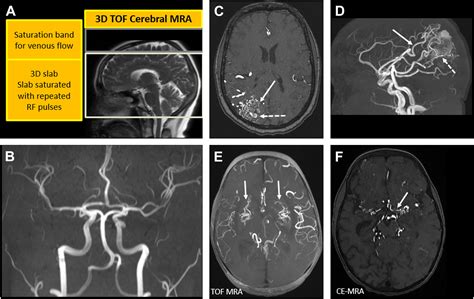

Magnetic Resonance Angiography (MRA) is a specialized application of MRI technology specifically designed to examine blood vessels. While a standard MRI looks at anatomy, an MRA is focused on hemodynamics—the way blood flows through your circulatory system. By manipulating the MRI machine's settings, doctors can highlight blood vessels and create a map of the vascular network.

MRA is primarily used to detect issues such as aneurysms, arterial blockages, narrowing of the vessels (stenosis), or vascular malformations. It is particularly valuable for identifying risks of stroke or heart disease. Because MRA provides a 3D visualization of blood flow, it acts as a critical tool for surgeons and radiologists planning interventional procedures.